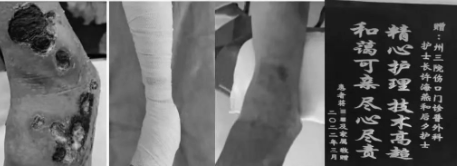

还有患者蒋某某,左下肢下肢静脉溃疡反复发作一年余,多处寻医未果,家属听说红河州第三人民医院伤口门诊能治疗各种慢性伤口,于是抱着“试试看”的心情,于2022年1月18日到伤口门诊就诊,采取压力疗法联合静脉溃疡敷料治疗下肢静脉溃疡,2个月后溃疡完全愈合,家属送来了感谢的锦旗,感叹到:“原来最好的医院就在我们身边,无需舍近求远到处寻医。”